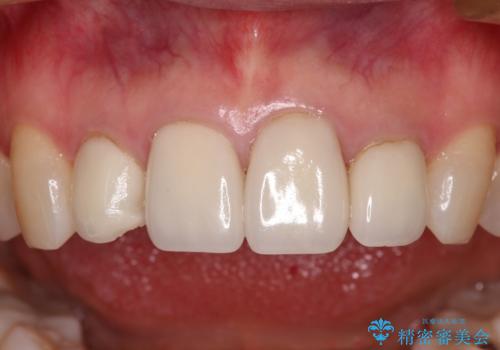

欠けてしまったセラミッククラウン 周囲のクラウンと同様の色彩で再製作

- 上顎4前歯に装着されているセラミッククラウンのうち、ひとつが欠けてしまったとのことで来院された患者様です。

土台となっている歯には問題がないため、周囲のセラミッククラウンと色調が合うように、オーダーメイドタイプのセラミッククラウンにて補綴治療を行うこととしました.

欠けてしまったセラミッククラウンはガラス系セラミッククラウンであったため、今回製作する歯は、強度の強いジルコニアセラミッククラウンとしました。

クラウンの種類は異なりますが、色調の適合したクラウンを装着することができました。